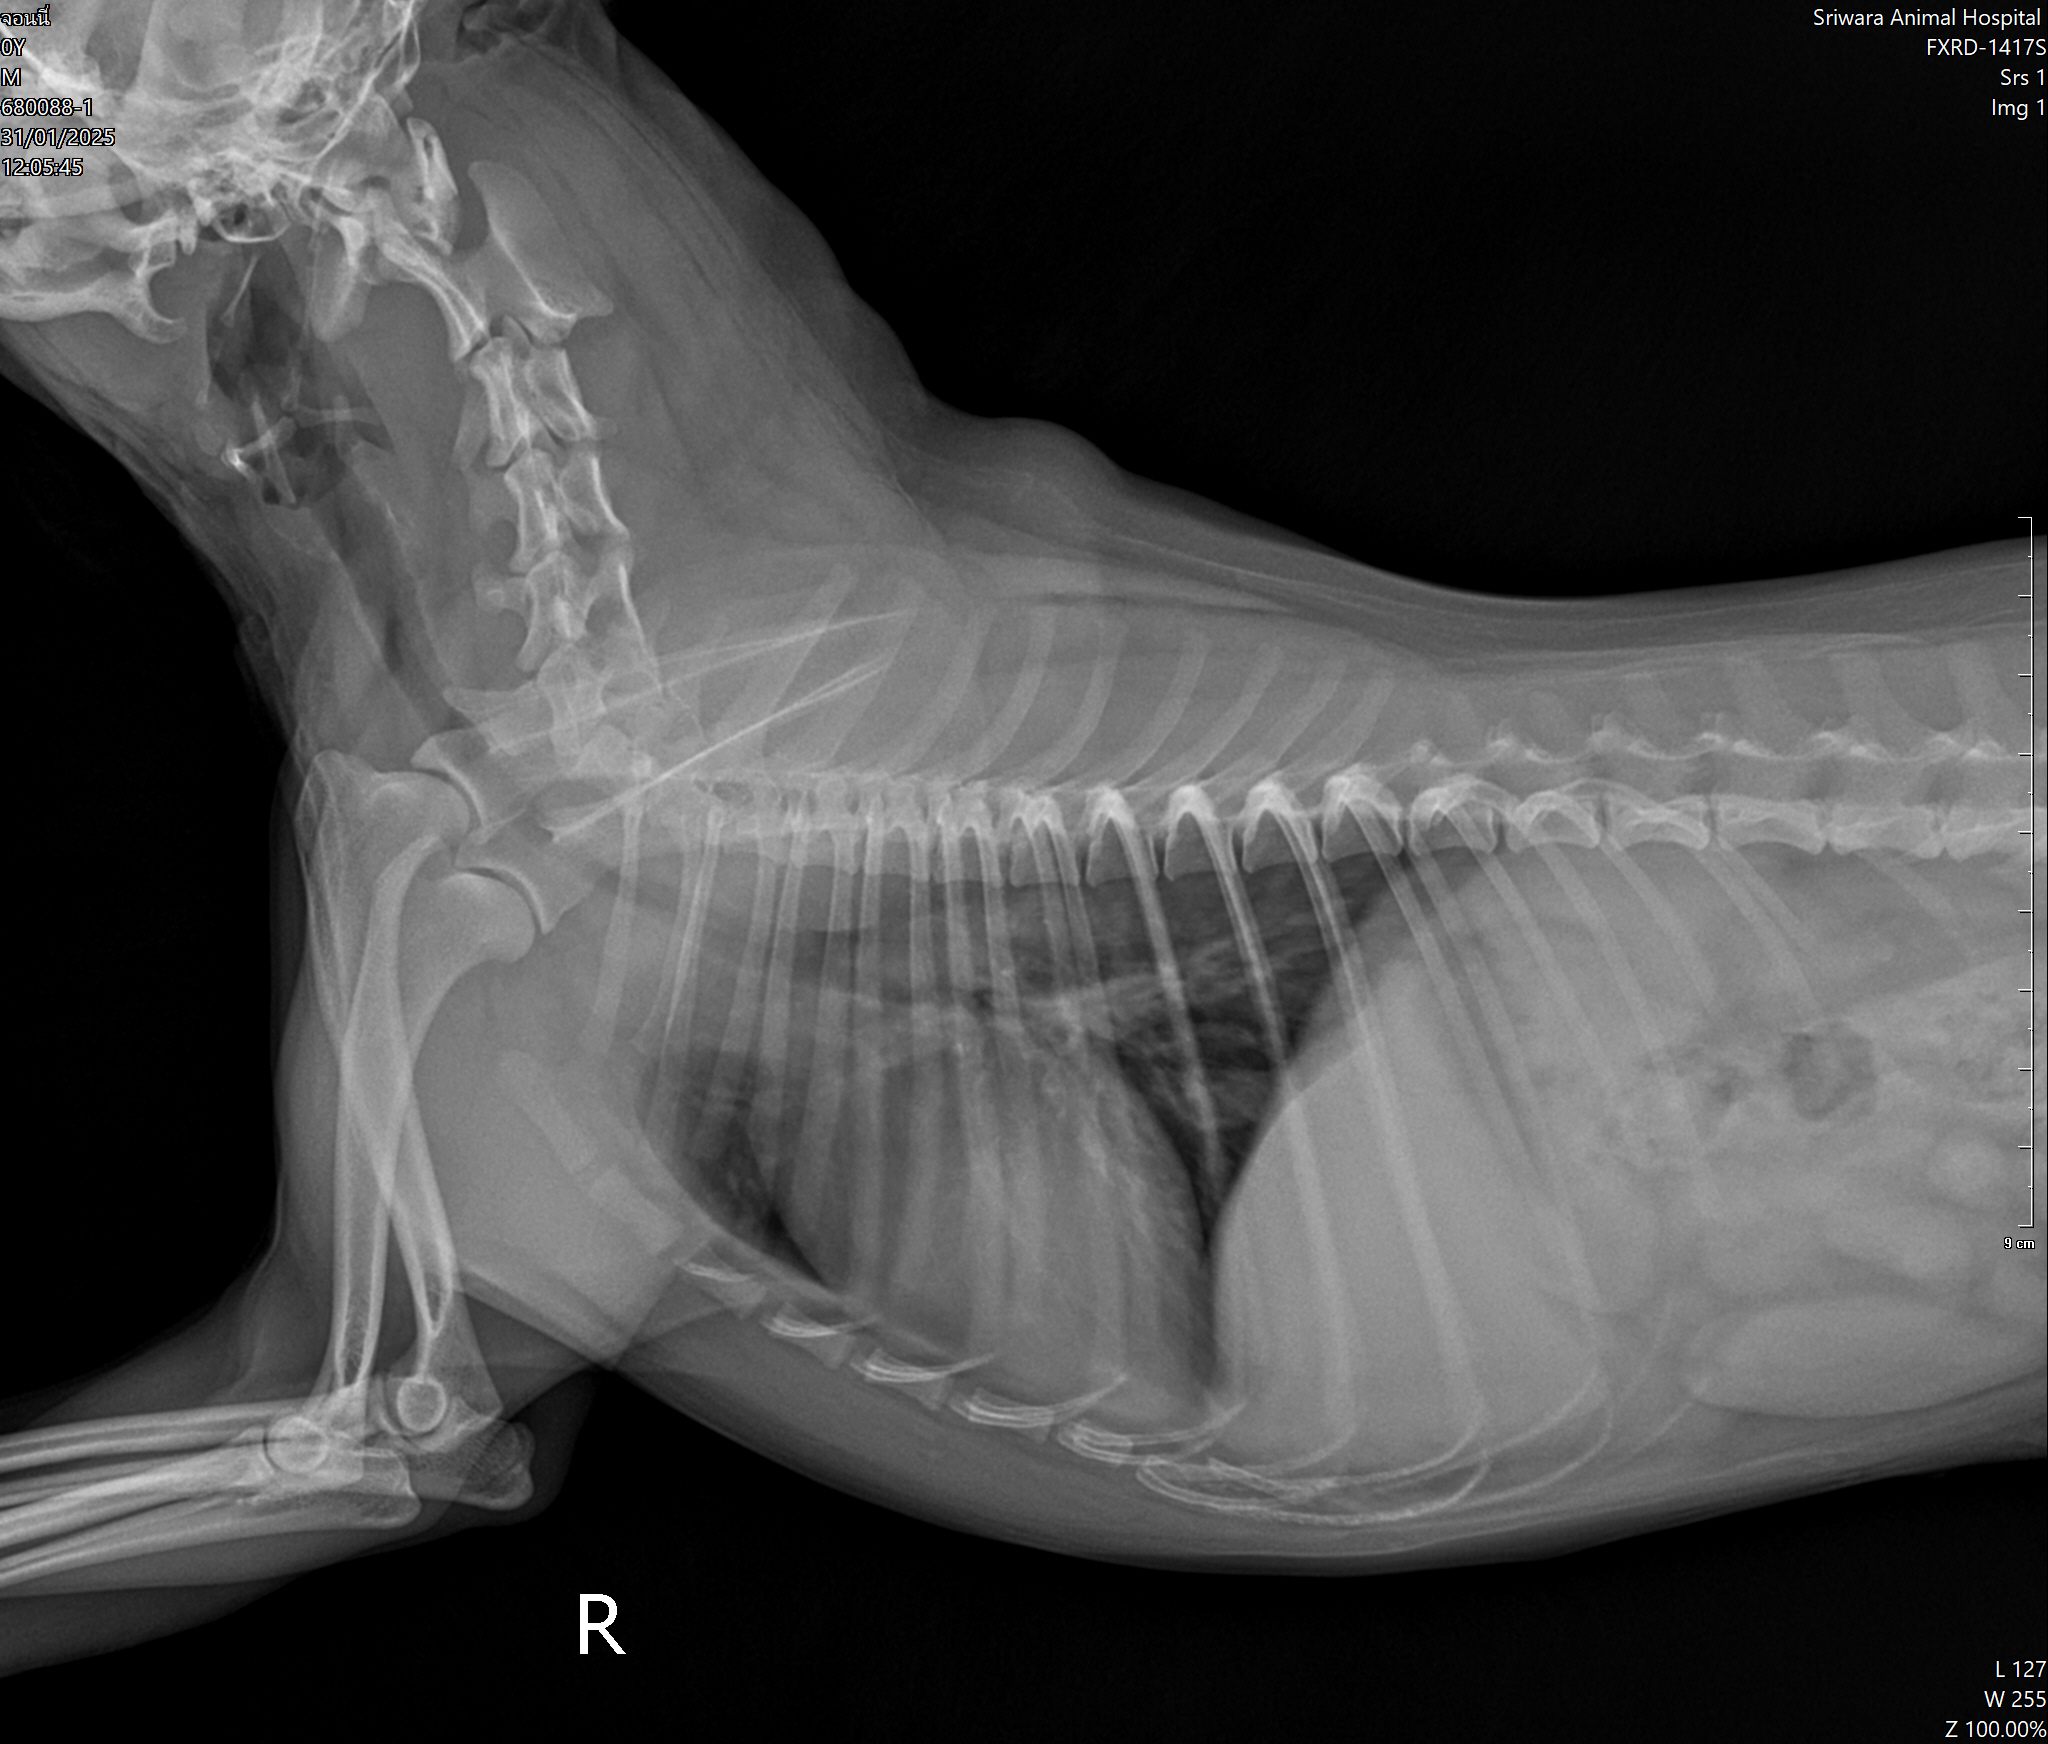

- ไอเสียงเหมือนห่าน ไอหนักช่วงตี 2-4

วินิจฉัย

- หลอดลมอักเสบ

- ไอ หายใจไม่ออก นอนไม่ได้ ลิ้นม่วง

วินิจฉัย

- น้ำท่วมปอด

- หลอดลมตีบ